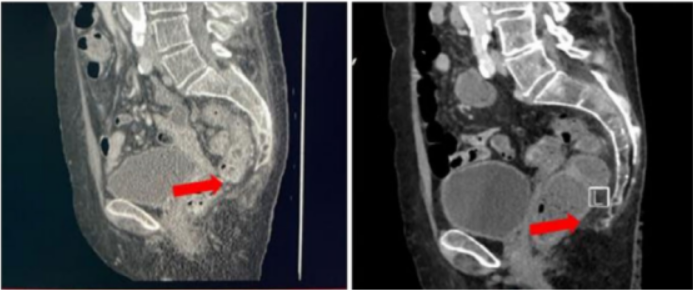

图3 | 患者3接受匹妥布替尼治疗的影像学表现:CT在基线期(左图)及治疗1个月时(右图)的对比

85岁确诊BNS,患者因病情急剧恶化伴活动能力下降收治入院。CT扫描和脊髓MRI显示骶管占位,至少延伸到S3-S4过渡段,长TR序列呈低密度,脑脊液检出淋巴浆细胞(流式细胞术)。

患者在接受匹妥布替尼200mg治疗的首个月期间,运动功能出现部分恢复;治疗1个月时的CT扫描显示病变组织完全消退,血液学反应PR。